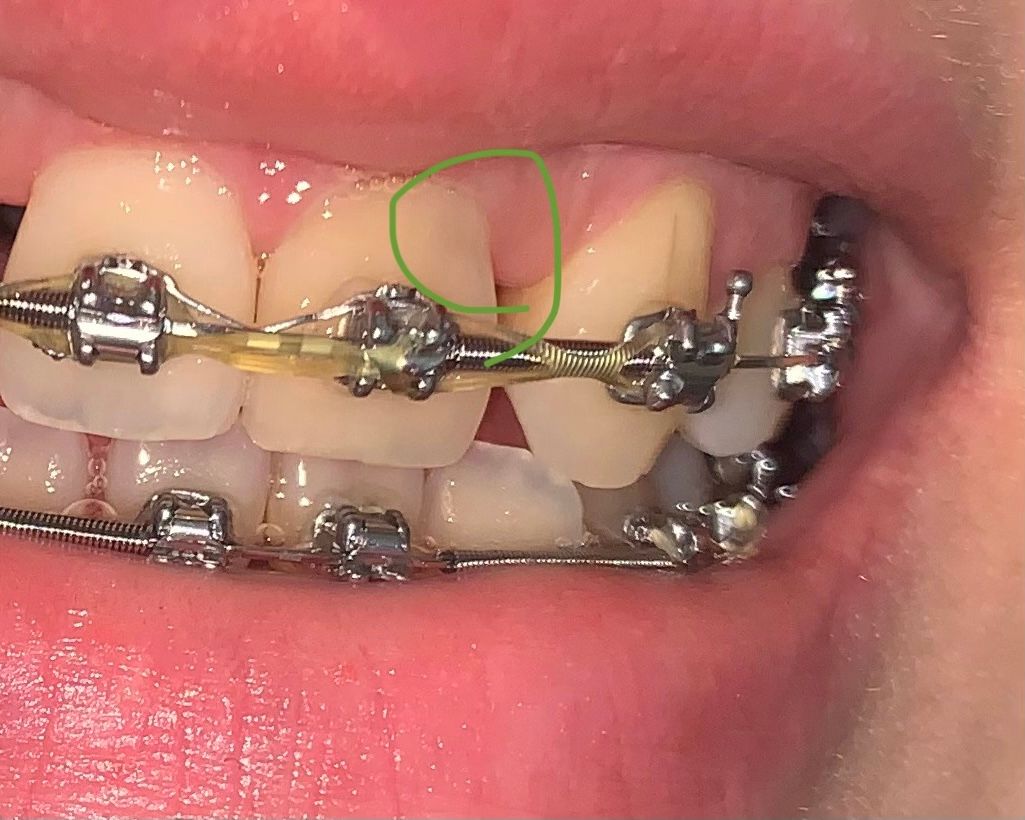

치아사진과 파노라마(교정 전 것이지만 상태는 현재와 동일) 보시고, 검은색으로 비치는 게 뭔지 알려주시면 감사하겠습니다!! 확실하지 않아도 되니 의심되는 것 전부 말씀해주시면 감사하겠습니다..!ㅜㅜ

치아 사이에 보이는건 변색이 아니라 치아 사이 공간이 넓어지면 까맣게 보이는게 아닐까 싶습니다. 그리고 아래 보이는 치아 뒷부부분은 충치가 진행된거 같습니다.

방사선 사진 상 해당 치아에 외부충격의 외상이든, 앞니로 딱딱하거나 질긴 것을 세게 물었든 힘이 가해져서 치수강 위축이 생긴 상태입니다 이로보아 변색은 신경과 관련된 것이 높을 것으로 판단은 됩니다

치아 속 신경에 대해 ice테스트, 전기치수검사를 해보면 명확하게 알수 있긴 합니다